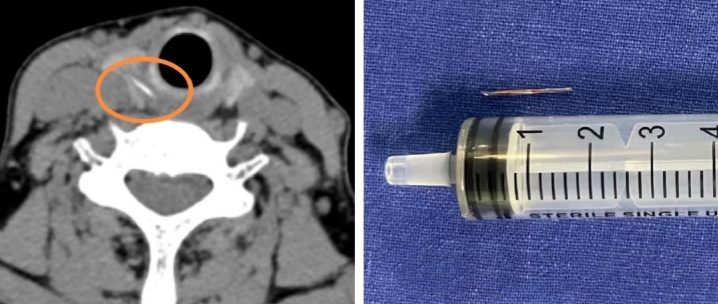

影像结果证实,在刘阿姨右侧甲状腺位置,发现了一条索状的高密度异物影,极有可能是鱼刺穿透食道壁,扎进了甲状腺。

手术中,医生小心翼翼地探入颈部,精细地分离组织,完好地保护了甲状腺、甲状旁腺以及喉返神经,最终成功从右侧甲状腺中,取出了一枚长约1.5厘米的鱼刺。